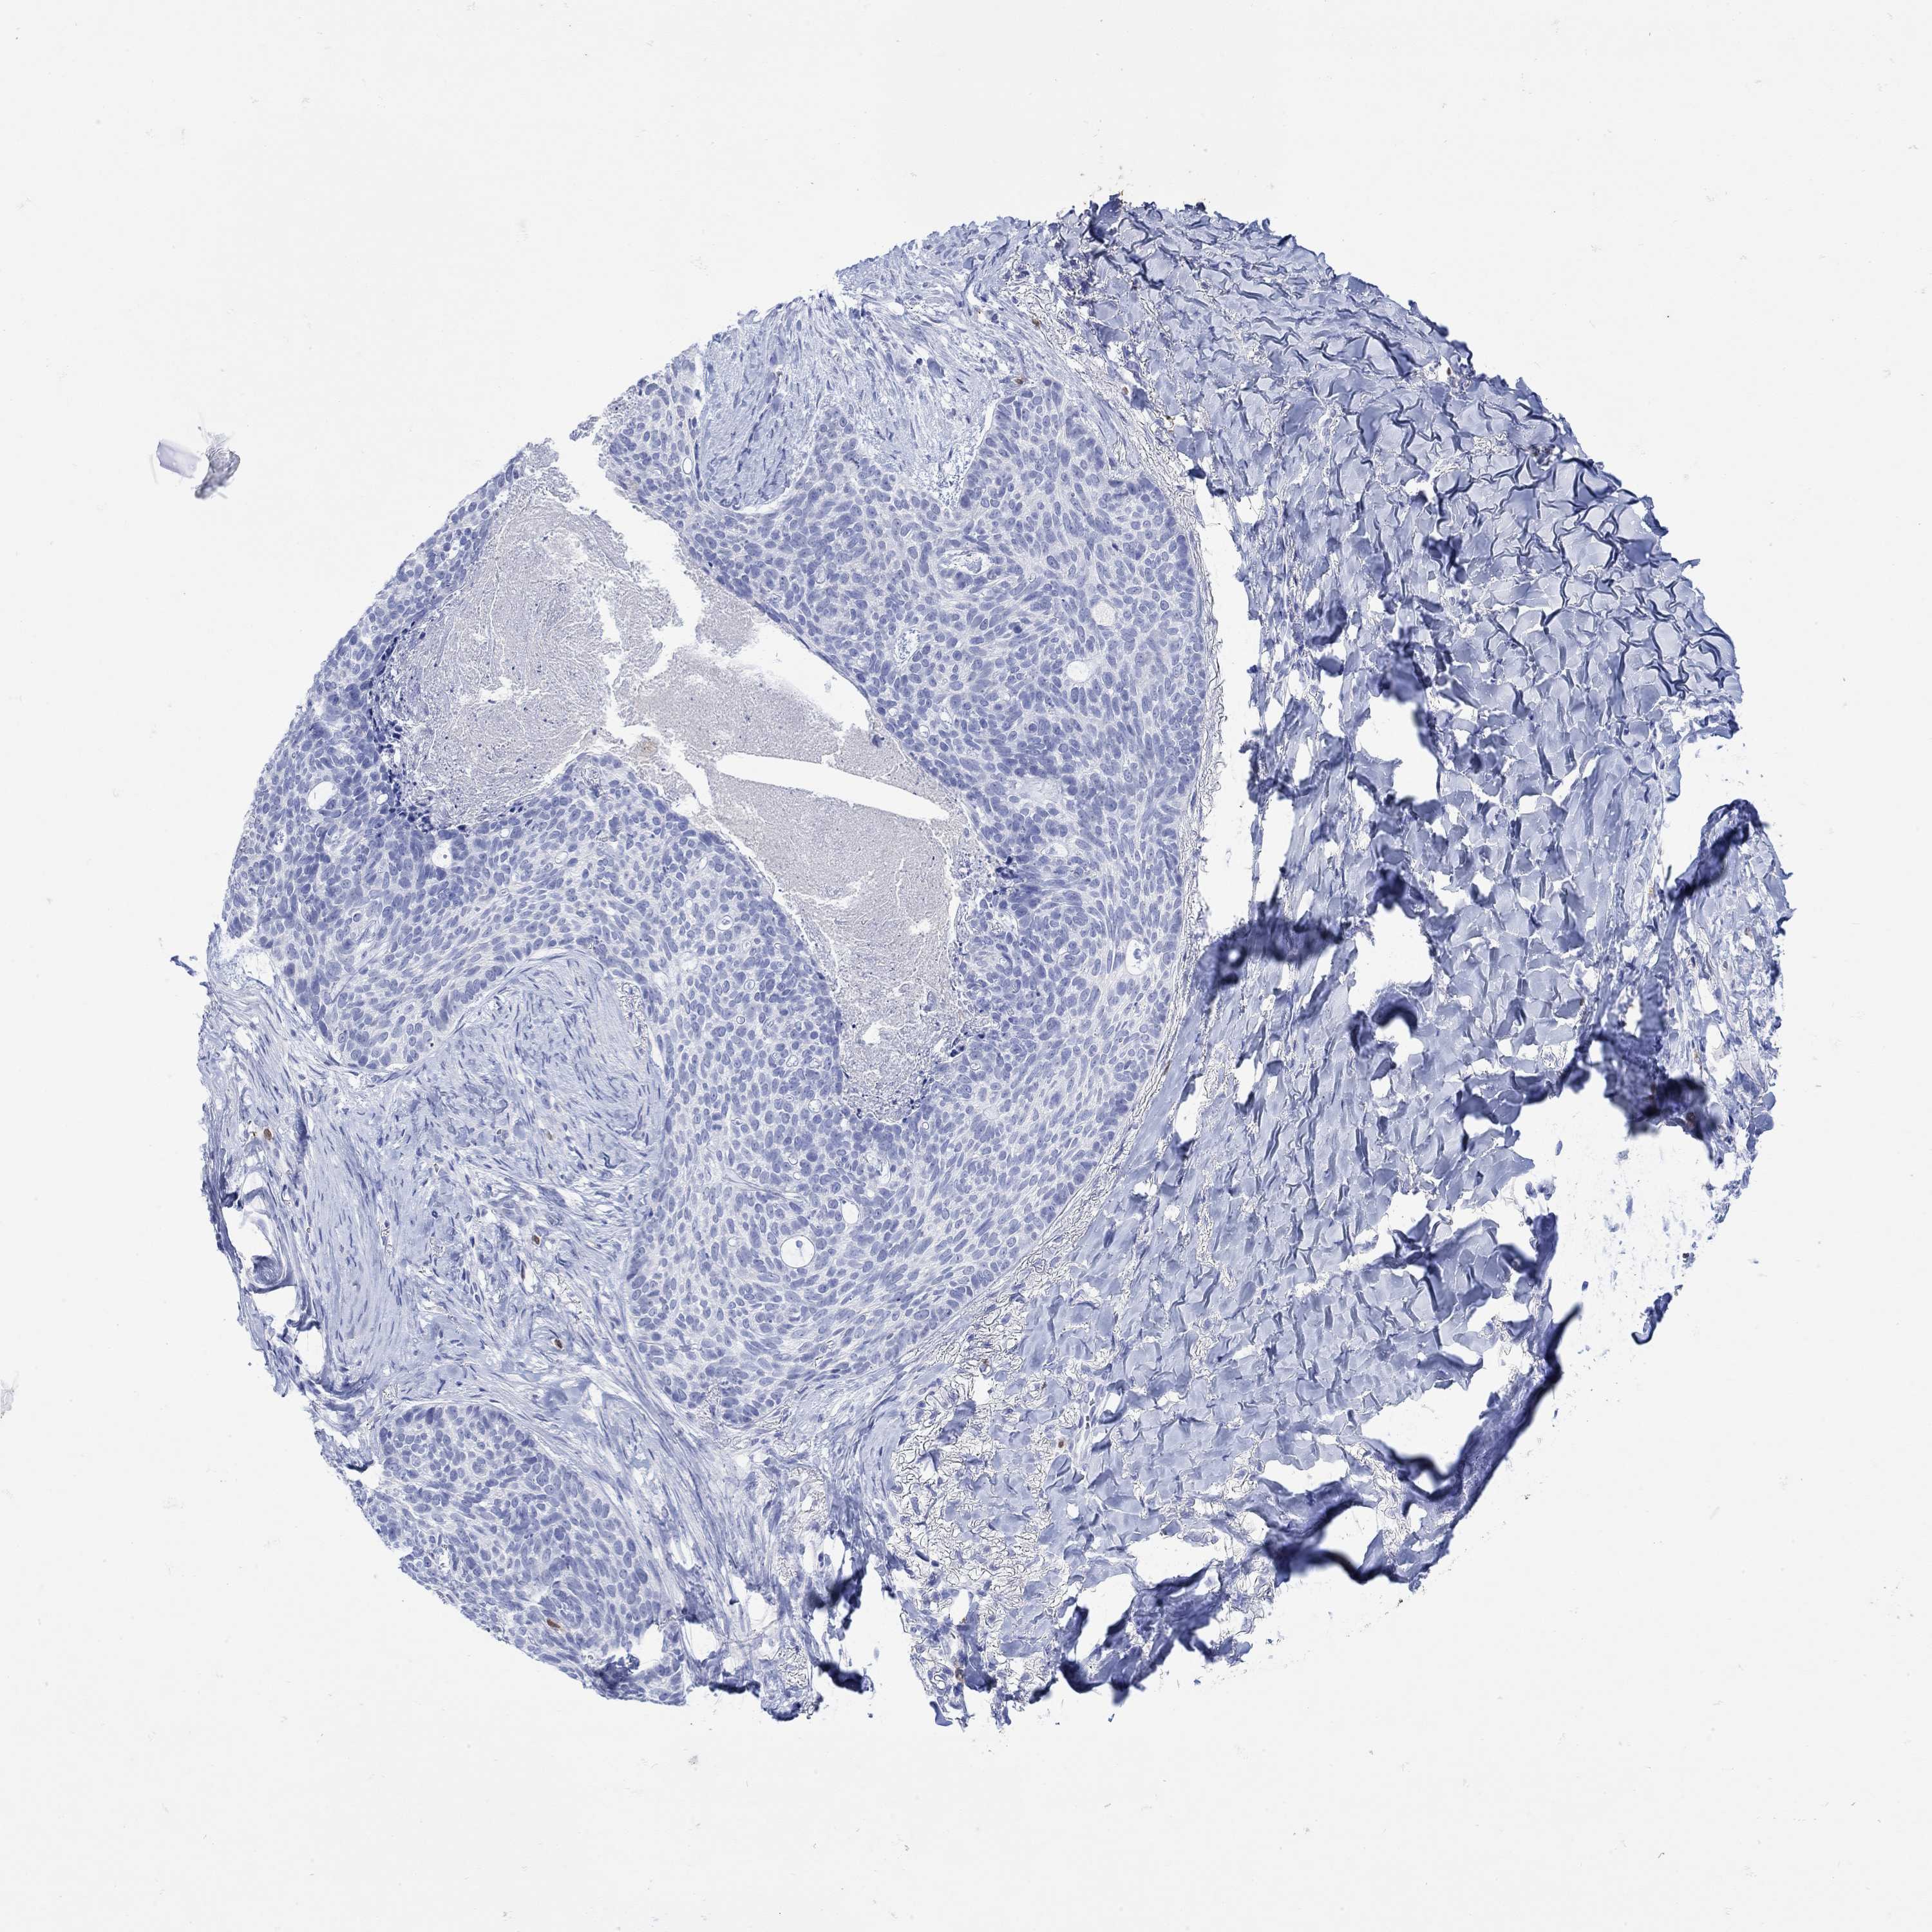

SKIN CANCER - Protein expressioni

A mouse-over function shows sample information and annotation data. Click on an image to view it in a full screen mode. Samples can be filtered based on level of antibody staining by selecting one or several of the following categories: high, medium, low and not detected. The assay and annotation is described here.

Antibody staining in the annotated cell types in the current human tissue is reported as not detected, low, medium, or high, based on conventional immunohistochemistry profiling in selected tissues. This score is based on the combination of the staining intensity and fraction of stained cells.

Each image is clickable and will lead to virtual microscopy that enables deeper exploration of all samples and also displays staining intensity scores, fraction scores and subcellular localization as well as patient and tissue information for each sample.

Antibody HPA059558

Staining

High

Medium

Low

Not detected

Intensity

Strong

Moderate

Weak

Negative

Quantity

>75%

75%-25%

<25%

None

Location

Nuclear

Cytoplasmic/membranous

Cytoplasmic/membranous,nuclear

Basal cell carcinoma

Squamous cell carcinoma, NOS